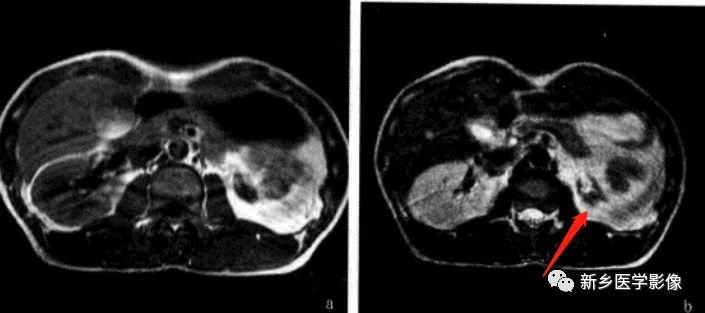

MR

肾不发育,仅为一小块肾脏,常误诊为孤立肾。多囊性肾发育不良,一侧肾区大小不等的囊肿液性水样信号,有薄厚不一的分隔,可伴发育不良肾结构,增强无强化,对侧肾和输尿管可正常。

讨论

肾发育不良与发育不全的临床表现取决于其累及的程度。常伴其他血管发育异常,检查应避免疏漏。诊断中,发现小肾结构非常重要。